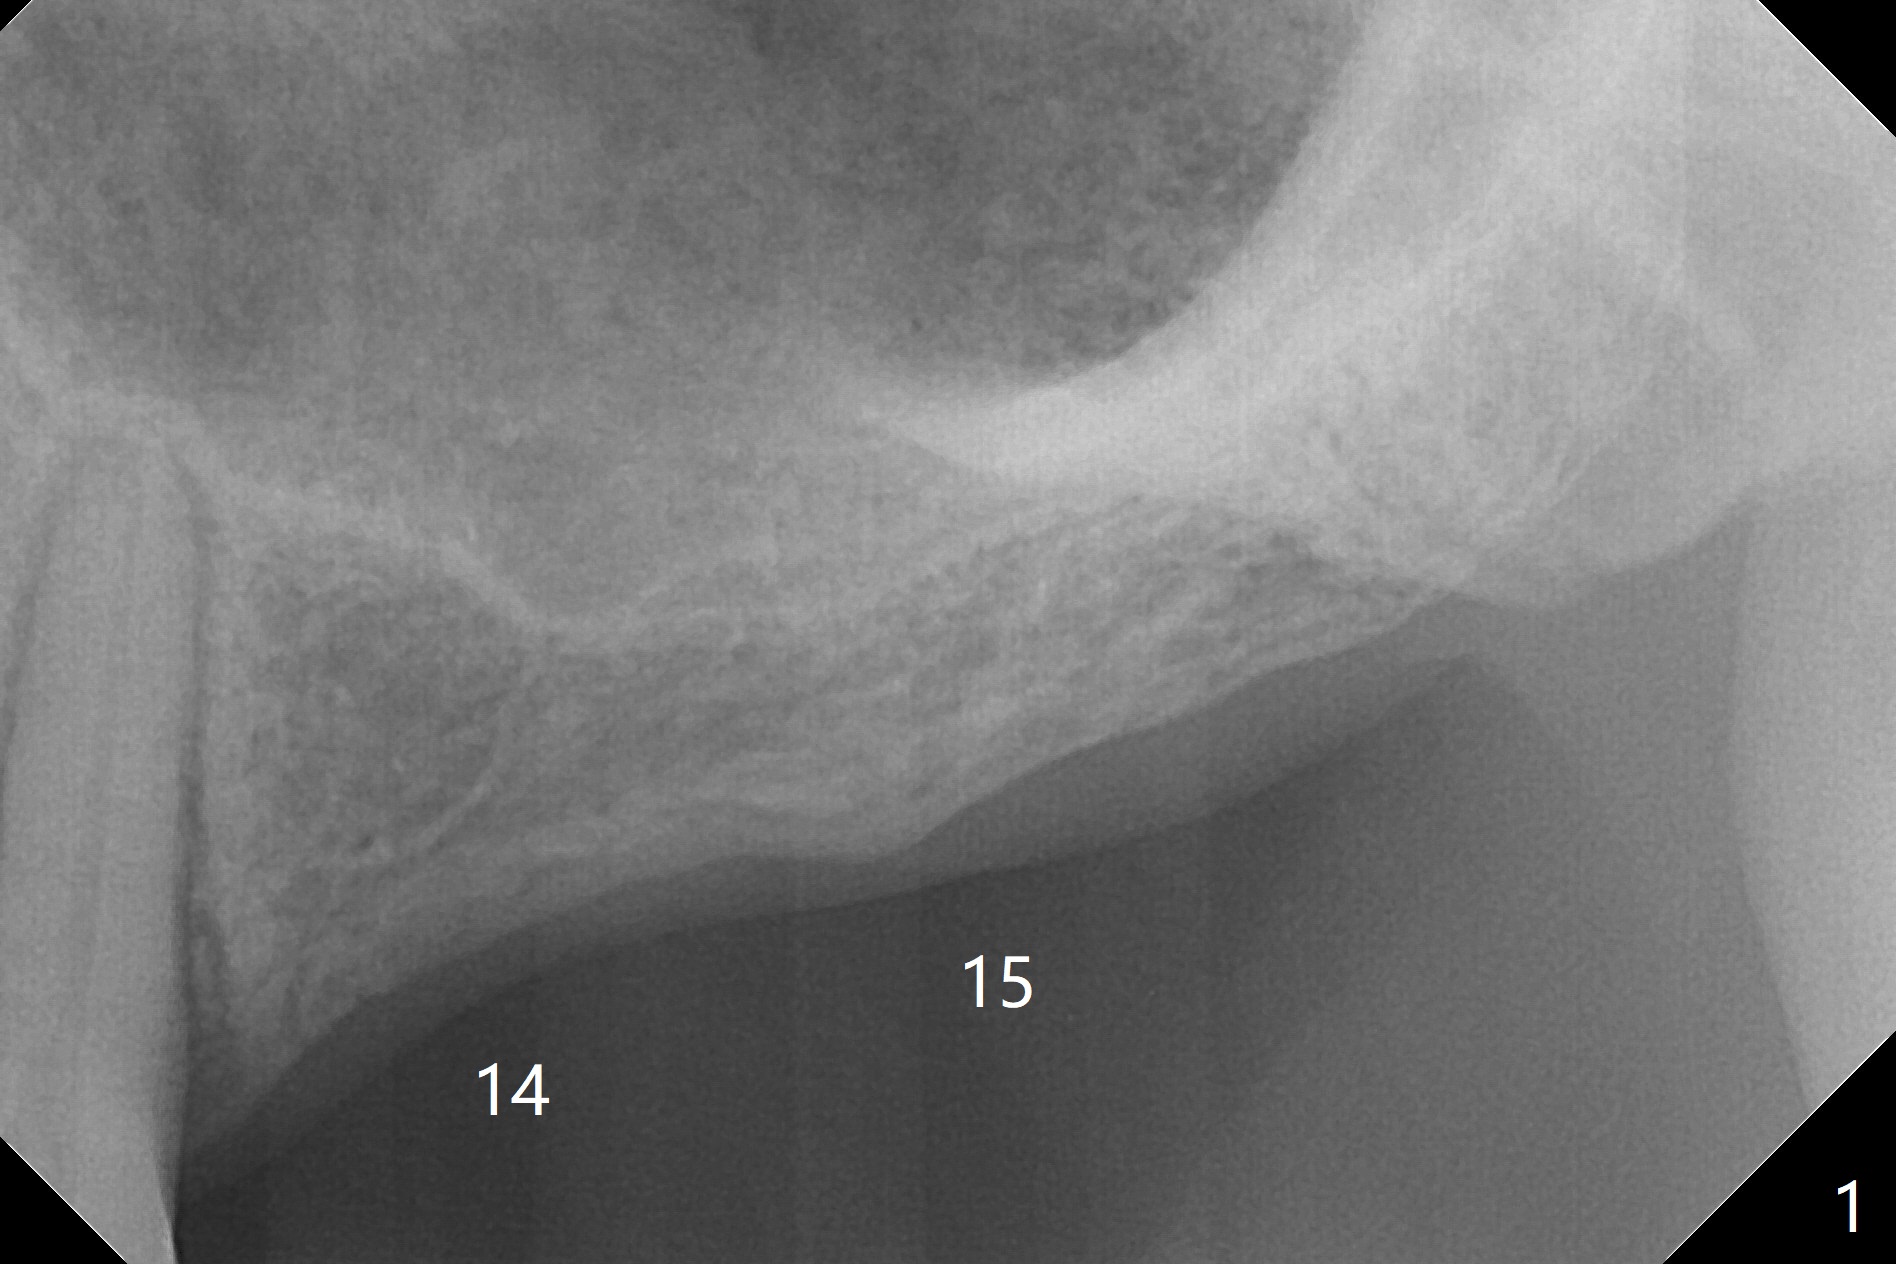

A 57-year-old woman has lost #14,15 and 18 for a while (Fig.1). Because of fear, an implant will be placed at #14 first (Fig.2). After use of Magic Drill for 5 mm (Fig.3), Magic Lifter will be used for lift (Fig.4). Following placement of PRF membrane (Fig.5 blue) and Vanilla Graft (red circles), a dummy implant is placed for additional lift (Fig.6 green). With placement of a larger and probably longer definitive implant, the graft may migrate distal due to gravity in sleep (Fig.7 arrow). In a few months, the bone height at #15 may increase to facilitate implant placement at #15.